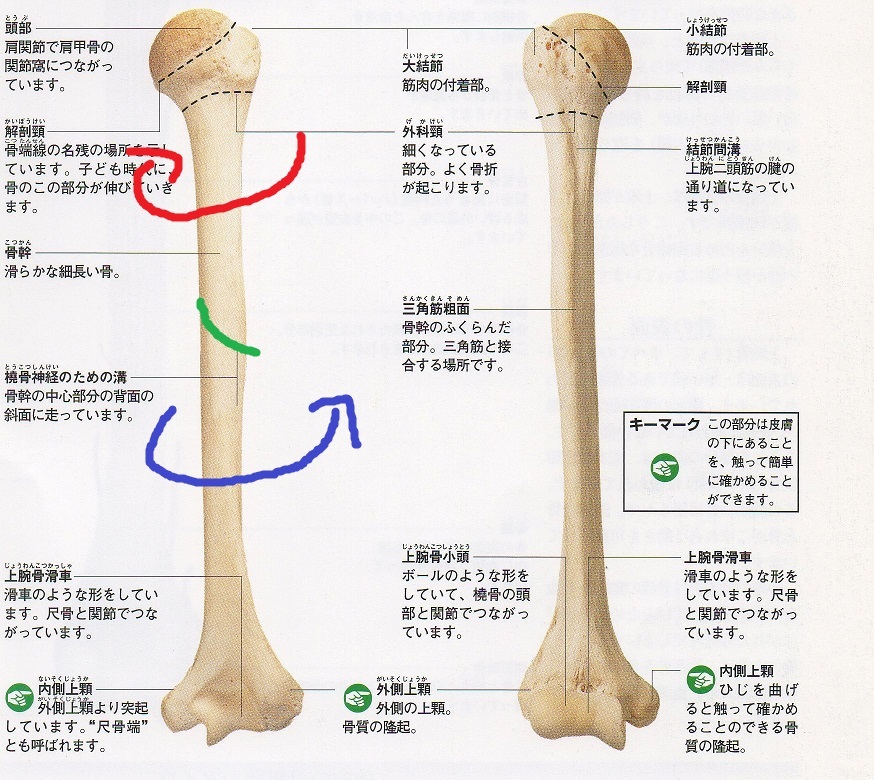

肱骨 Humerus 小小整理網站smallcollation

肱骨 Humerus 小小整理網站smallcollation

肱骨 Wikiwand

肱骨 肱骨 位於上臂 又叫上臂骨 上端有半球形的肱骨頭與肩胛骨的關節盂組 百科知識中文網

肱骨 维基百科 自由的百科全书